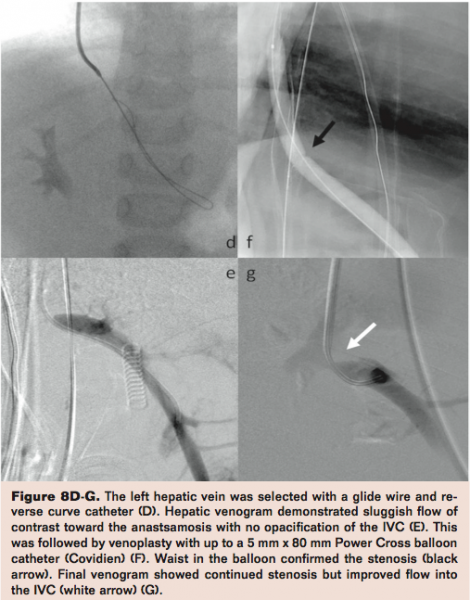

Hepatic Vein Stenosis

Hepatic vein stenosis (HVS) is a major post-transplant complication, especially in patients with partial liver graft transplantation producing graft failure with a reported incidence of 1% to 4%.5,27-29 Hepatic vein stenosis leads to hepatic congestion; manifestations include refractory ascites, refractory hydrothorax, and alteration of LFTs. Hepatic vein stenosis is most frequently seen at the site of the anastomosis and is less frequently seen in the hepatic vein itself. In the presence of clinical or radiologic suspicion of HVS, selective catheterization of all hepatic veins is necessary to confirm stenosis and to measure the trans-stenotic pressure gradient. Pressure gradients greater than 3 mmHg between the hepatic vein and the right atrium are considered pathological.29 For treatment of HVS, percutaneous interventions have adequate clinical and technical success rates. The initial treatment of choice is transjugular or transfemoral angioplasty or metallic stent placement.27-29 For example, in our case of hepatic venous stenosis, a 2-year-old who had previously undergone retransplantation benefitted from a dramatic reduction of the gradient from 15 mmHg to 4 mmHg, which was achieved with venoplasty (Figure 8). Multiple interventions may be required for long-term sustained patency, including the use of endovascular stent placement.30-32